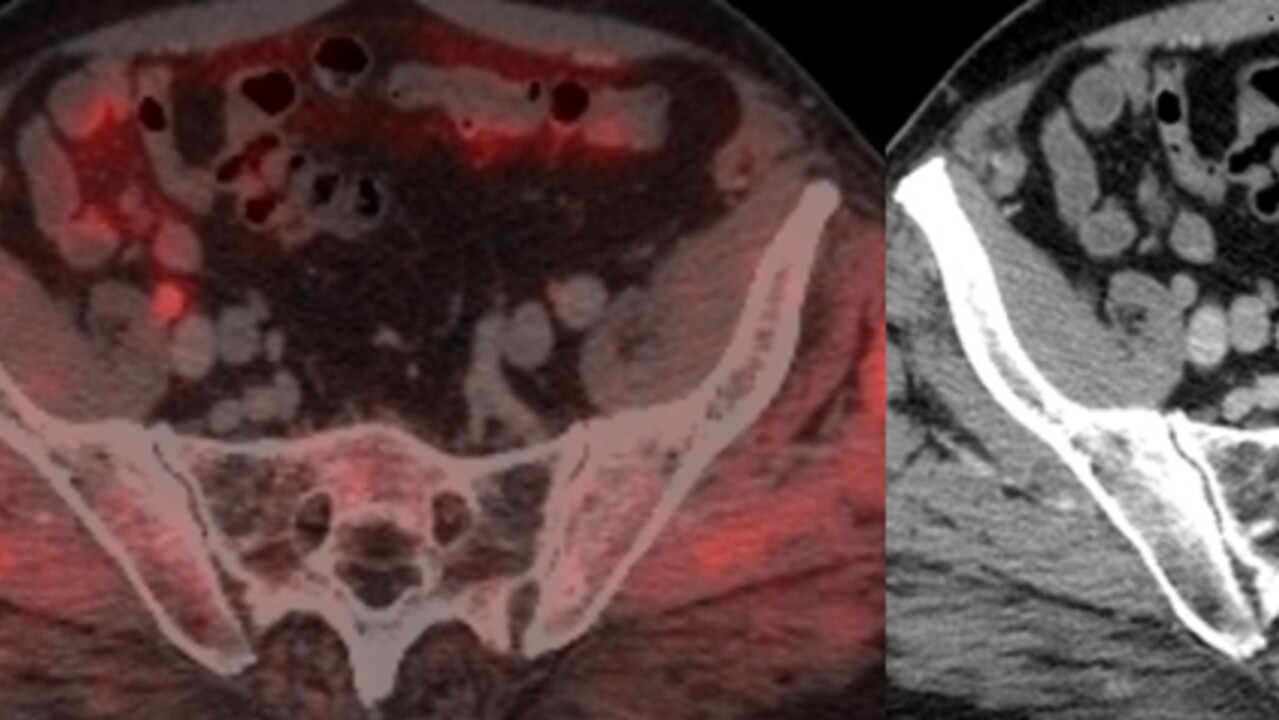

Sara Strandberg, Institutionen för strålningsvetenskaper, försvarar fredag 27 mars kl. 9.00 sin avhandling 11C-acetat-PET/CT vid primär stadieindelning av prostatacancer av högrisktyp.